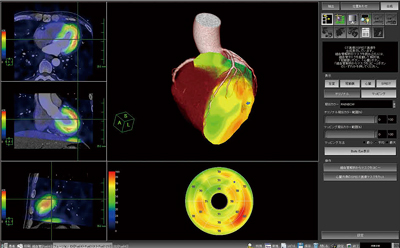

3.CTコロナリー画像と心筋シンチグラフィ画像の3Dフュージョン

AZE VirtualPlaceでは,先進的な画像位置合わせアルゴリズム(アトラス法)を用いて,CT画像とRI画像の自動位置合わせを行うことができる。従来の位置合わせアルゴリズムでは,CTの高い解像度の画像とRI画像との間の共通点を見つけることが難しく,その結果,好ましい位置合わせ結果を得ることができなかった。これを解決するために,新しいアルゴリズム(アトラス法)では,CT画像とRI画像の双方の間に平均的な情報(アトラスデータ)を用い,CT,RIのデータをそれぞれアトラスデータに近づけることにより,位置合わせの精度を格段に向上することに成功した。このアルゴリズムを使用して位置合わせを行った画像を,CT冠動脈解析のコロナリー像と重ね合わせることで,虚血の広がりとその責任血管の位置関係を,容易かつ正確に認識することができる(図5)。

図5 CTコロナリーとシンチグラフィの3Dフュージョン画面